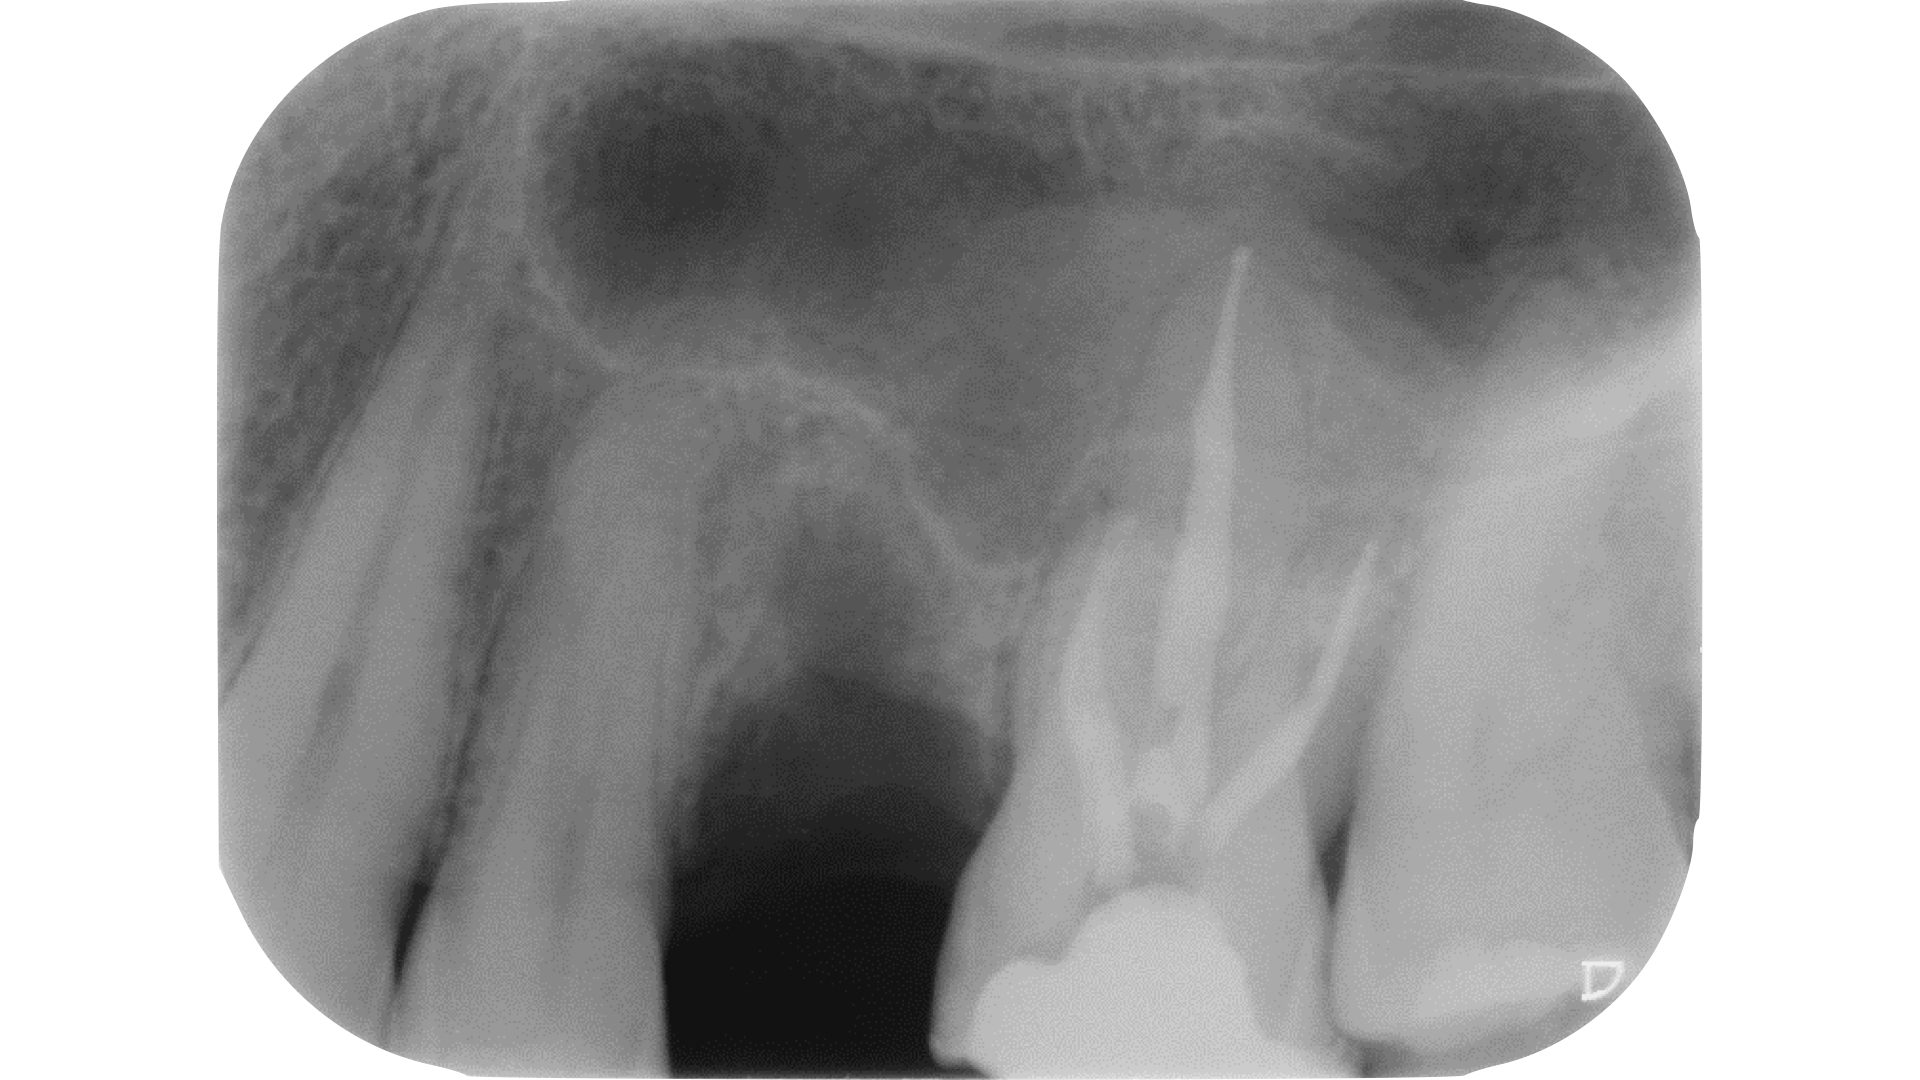

Qualora invece l’ostruzione si estendesse più in profondità, la regola della polvere dentinale può servire come guida per il clinico. Questa regola trae il suo fondamento da una delle leggi di Krasner e Rankow7, quella del cambio di colore.

Il sistema canalare è sempre contenuto in un’area più scura rispetto alle pareti canalari e quindi l’azione di avanzamento è guidata proprio da questo assunto cromatico.

Consumando lentamente dentina in direzione apicale (a secco, a basso numero di giri, raffreddando con la siringa ad aria) pochissimi decimi di millimetro per volta si manterrà la corretta centratura all’interno della radice e si potrà visualizzare ad un certo punto una traccia bianca: non si tratta altro che di polvere dentinale prodotta dall’azione dello strumento rotante che si deposita in maggiore quantità proprio in corrispondenza della traccia dell’orifizio.

Lo strumento ideale per avanzare alla ricerca del canale è ancora una volta Endotracer. Il gambo lungo (disponibile anche nella versione 34 mm, oltre che 31 mm) consente di poter avere sempre controllo visivo sull’avanzamento.

I diametri utilizzati vengono scelti in base alla profondità: via via che si procede apicalmente è necessario ridurre il diametro e anche la velocità di utilizzo, oltre che fare pause di controllo sempre più frequenti.

Questa azione di consumo selettivo della dentina può rendere visualizzabile in tempi molto brevi la traccia “bianca” di polvere depositata sull’orifizio; qualora invece i primi passaggi non avessero reso possibile la localizzazione è opportuno alternare irrigazione con ipoclorito di sodio e asciugatura per poi ripartire con un nuovo ciclo di escavazione (Figure 27-33).

Una volta localizzata la traccia del canale è necessario cercare di sondarlo anche per pochi millimetri con un micro opener o un K file di piccole dimensioni 06 o 08.

In questa fase di esplorazione va riposta molta attenzione nell’evitare di ostruirsi di nuovo la strada in direzione apicale: questo è possibile grazie a ripetuti lavaggi e alternanza di tentativi di sondaggio manuale senza forzare e affrettare la discesa fino a lunghezza di lavoro. A differenza degli inserti ultrasonici che tendono a creare un invito spesso appuntito in direzione apicale e ad annullare almeno parzialmente le tracce cromatiche, l’utilizzo di strumenti rotanti strategici come Endotracer preserva questi fondamentali punti di riferimento e anzi facilita l’accumulo di detriti dentinali proprio dove c’è una naturale depressione, vale a dire il lume canalare.